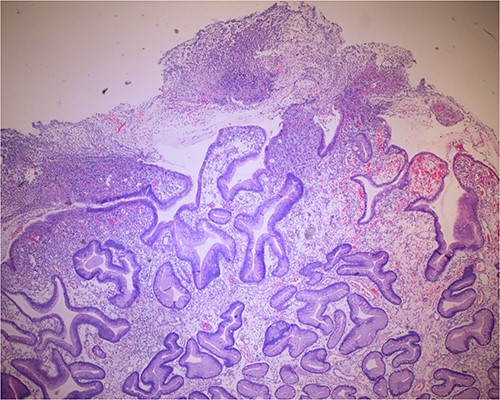

Histologic sections of the polyps demonstrated benign gastric hyperplastic polyps with acute and chronic gastritis (Fig. 2). Portions of the gastric polyps and adjacent mucosa were covered by inflammatory cell exudate (Fig. 3). Higher magnification revealed conspicuous volcanic-like eruption of the exudate, reminiscent of pseudomembranous gastritis (Fig. 4). Alcian yellow and GMS stains were negative for Helicobacter pylori and fungal organisms, respectively.

Biopsy of the polyp, covered in part by pseudomembranous inflammatory exudate.